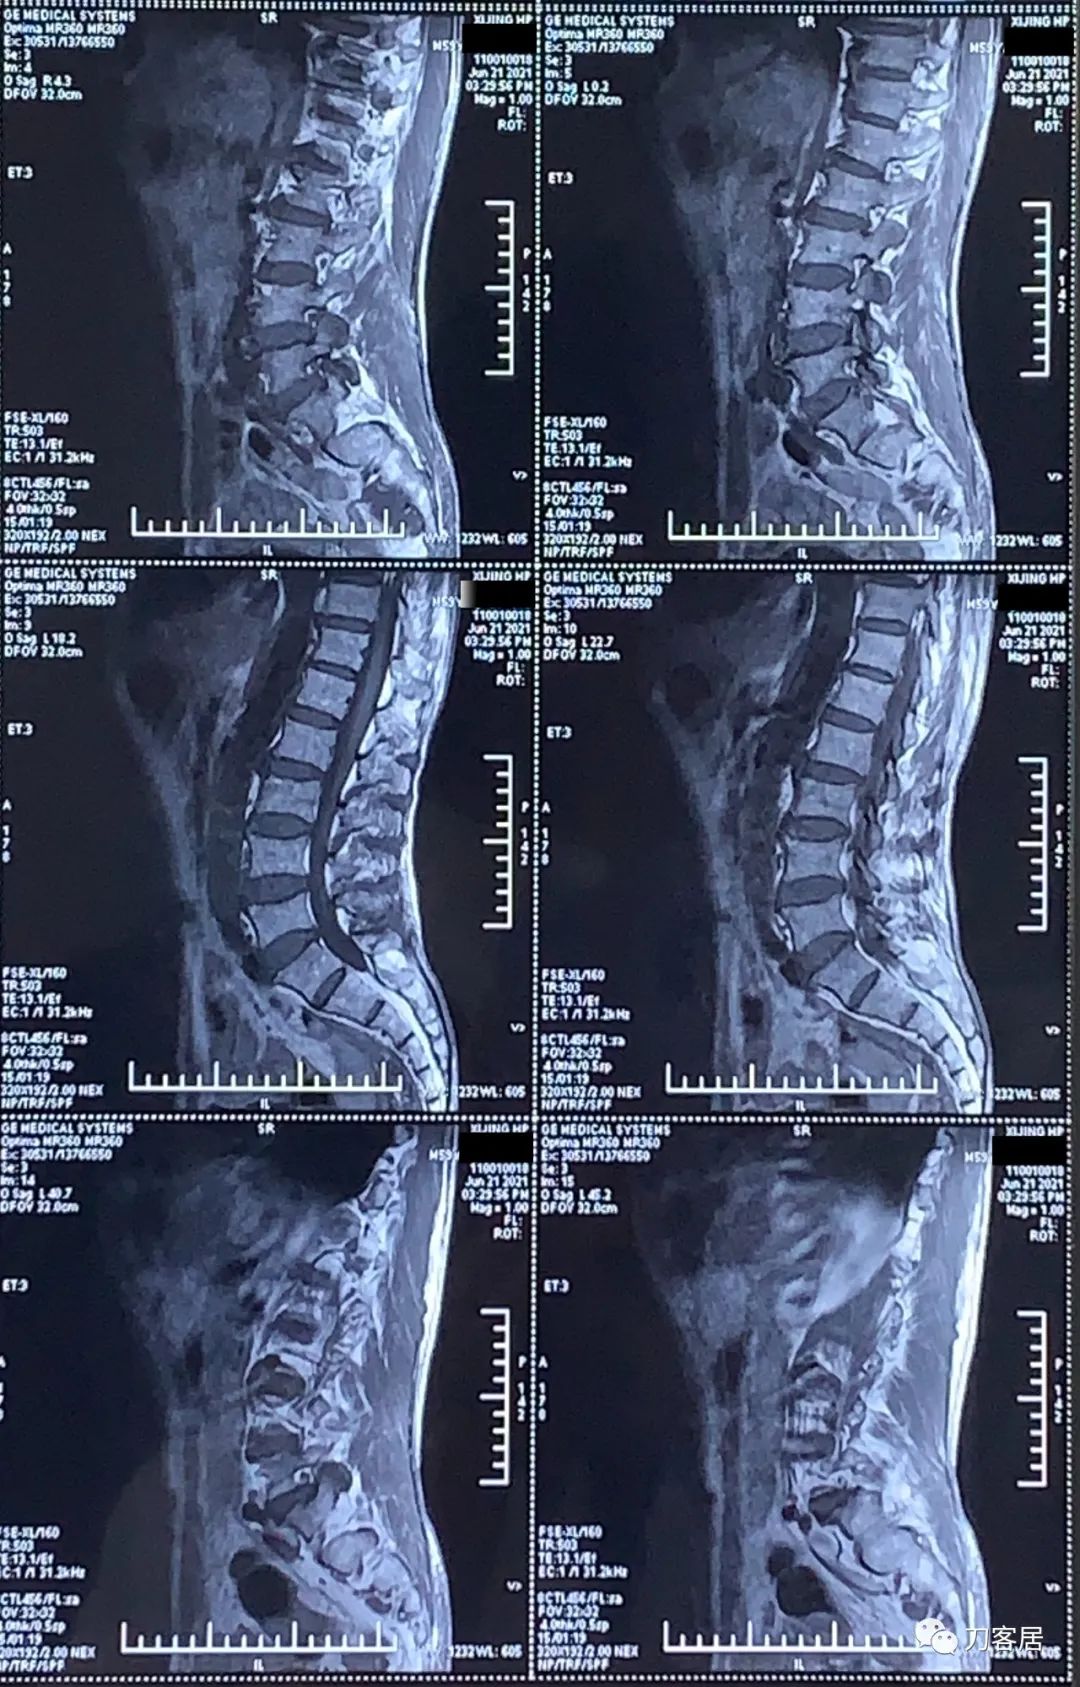

图5. 20210621西京医院腰椎MRI03

图6. 20210621西京医院腰椎MRI04